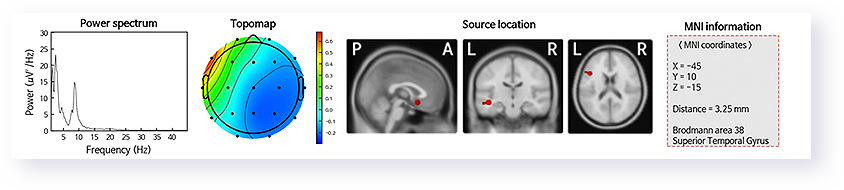

Brain mapping or qualitative electroencephalogram is a state-of-the-art, non-invasive diagnostic tool that allows visualizing brain electrical activity through brain waves. It detects areas of the brain that may not be functioning properly, providing 3D images of the brain.

It utilizes advanced software that processes EEG activity recorded from multiple electrodes using a computer.

The information derived from QEEG is interpreted and used by experts as a clinical tool for both diagnosis and treatment progress assessment. It allows tracking changes in brain function due to various interventions such as neurofeedback, psychotherapy, and/or medication. This provides objective information about the changes brought about by a specific treatment.